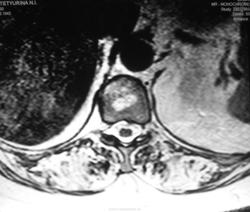

Пациентка - мама нашего коллеги. Жалобы на боли в позвоночнике.

Не опровергая мнения Евгения Второго: а не выглядит ли то, что "не красиво" в верхнегрудном отдлеле как "артефакты"? Складывается впечатление, что "изменения" с тел позвонков переходит на средостение и на грудину... Картинка как бы в "градиенте"... По остальному позвоночнику - дегенеративные изменения + гемангиомы + последствия компрессионного перелома тела позвонка; возможно ошибаюсь... Нужно смотреть шейно-верхнегрудной...

Спондилит туберкулезный..

спондилит то есть, с компрессией тела позвонка и паравертебральными изменениями. и если вверху артефакты (граница каналов катушки, неправильное позиционирование или типа того) - тогда спондилит выходит на первый план. только насчёт туберкулёзного я бы не стал так уж уверенно. может просто опыта нет в дифдиагностике туберкулёзного и банального спондилитов (у меня).

Компрессионный перелом позвонка, вокруг изменения мягких тканей, похожие на натечник. Хотя рассмотреть бы это в нормальном качестве... DICOMа нету?

Тактически наиболее правильно исходя из имеющихся данных выполнить транспедикулярно под контролем просвечивания трепанобиопсию тела позвонка.

Я не занимаюсь сам, этими прекрасными высокими технологиями. После исследования, проведенного в области были выставлены множественные гемангиомы. Боли в позвоночнике у пациентки были и ранее, но в определенный момент резко усилились, по всей видимости, тогда и произошла "компрессия". Мне не верится, что это гемангиомы. Я более склонялся к специфике (туб спондилиту), но это мнение во многом больше интуитивно.